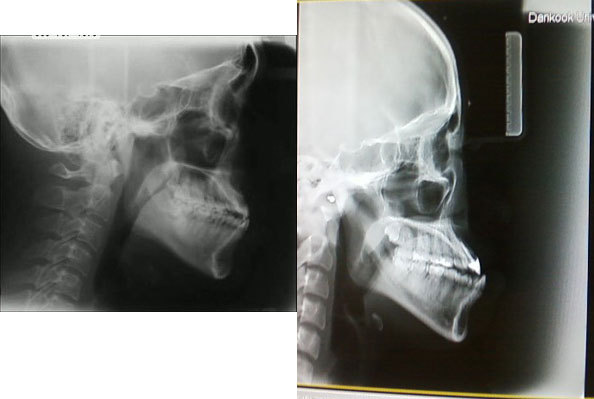

아까 위에서 나온 양악수술 부작용 오빠의 수술전 내 X-ray사진.

여기서 뭘 봐야하는지 알아??

일단 나랑 저 오빠 모두 주걱턱인것과, 윗턱 치아의 각도를 봐봐.

둘 다 비슷하지?

이건 나랑 이 오빠가 주걱턱이라 그런건데,

원래 정상인의 각도는 95도? 이정도 일거야. 거의 직각에 가까운.

근데 나랑 저 오빠는 60도정도밖에안되지??

저 오빠의 부작용은 아마 저기서 거의 다 왔을거야.

윗 설멍처럼, 양악수술은 윗턱을 잘라서 먼저 집어넣은다음에,

아랫턱을 윗턱에 맞게 잘라서 넣는거야.

수술할 때 윗턱때문에 거의 좌지우지한다고 볼 수있어.

근데 저 오빠는 윗이빨이 첨부터 누워있잖아?

정상각도에 맞춰서 한게 아니라

이미 잘못된 윗턱을 가진 상태로 수술을 하니 잘못될 수밖에.

저런 경우는 교정을 먼저 들어가서

교정으로 윗이빨을 세워준다음에 수술을하지.

아마 저 오빠는 교정 먼저 했다면 양악 할 필요도 없었을거야.

교정하고서 하악 수술만해도 정상이 될 수 있었을텐데.

보면 나보다 주걱턱이 덜 심하잖아.